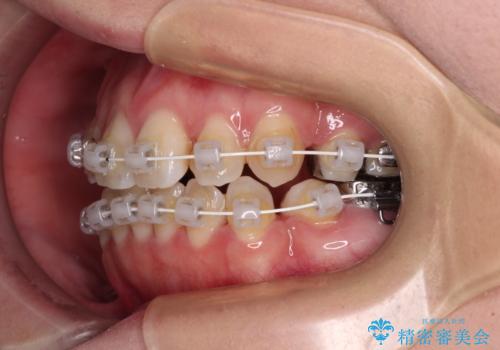

- 矯正装置

- インビザライン・審美装置

マウスピース(インビザライン)はほとんど使用することができませんでしたが、補助装置により上顎の八重歯は改善しておいたので、ワイヤー装置ではスムーズに治療を終えることができました。